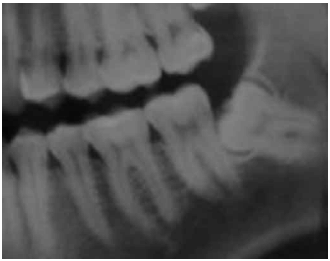

Uma paciente de seis anos de idade foi levada a um consultório odontológico para a realização de uma consulta de rotina. Ao examinar a arcada dentária da criança, o cirurgião-dentista observou que, apesar de ter havido a erupção do dente 11, ainda não havia ocorrido a erupção do elemento 21, conforme mostrado na figura I. Após a realização de radiografia da região periapical, constatou-se a presença de dente supranumerário impedindo a erupção do elemento 21, conforme apresentado na figura II, motivo pelo qual o cirurgião-dentista recomendou a remoção cirúrgica do dente supranumerário.

Tendo como referência as imagens apresentadas, julgue o item subsecutivo, relativo ao caso clínico descrito.

Após a exodontia do dente supranumerário, uma placa móvel mantenedora de espaço deverá ser utilizada até que ocorra a erupção do dente 21, a fim de aumentar o perímetro da arcada dentária e impedir o desvio da linha média.